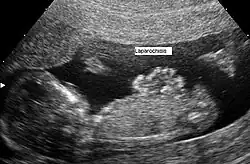

Gastrosquise (do greco-latim squise, fenda) também conhecida como laparosquise ou abdominosquise é uma má-formação congênita caracterizada por defeito na formação da parede abdominal, permitindo que as vísceras abdominais, como estômago e intestinos, saiam por uma abertura. Quase sempre ocorre à direita da região umbilical.[1]

Diferente da onfalocele, onde há envolvimento do cordão umbilical e os órgãos permanecem protegidos, recobertos por peritônio; na gastrosquise, as vísceras abdominais ficam soltas, não há membrana cobrindo os órgãos herniados, ficando portanto diretamente expostos ao líquido amniótico.

O nome "gastrosquise" é impróprio, já que a fenda compromete a parede abdominal, e não o estômago.[1] Laparosquise seria um nome mais apropriado.